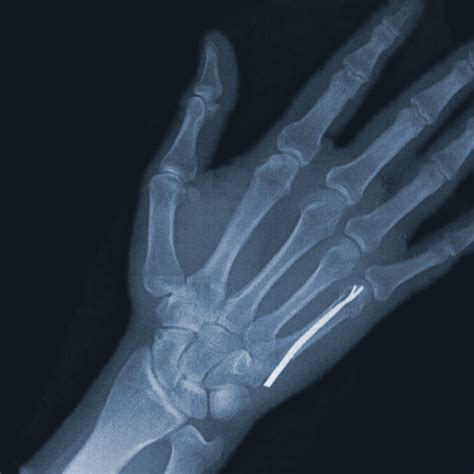

By this time, most uncomplicated fractures have formed a hard callus. X-rays may be taken to confirm that the bone is stabilizing. Your doctor might allow you to remove the splint for gentle, controlled movement. It is common to feel significant stiffness, but this is a normal part of the process.